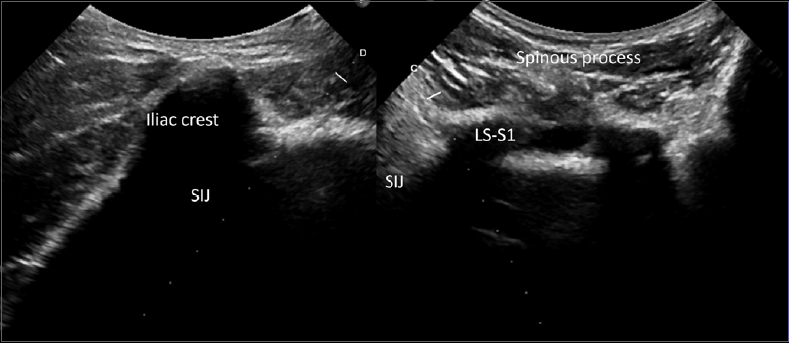

Figure 4.L5-S1 is easily located as the first horizontal laminas above the sacrum, aligned with the iliac crest and the sacroiliac joint. The guide directs the needle directly into the facet joint.

Figure 5.L4-L5 is located jut above, aligned with the upper tip of the iliac crest.